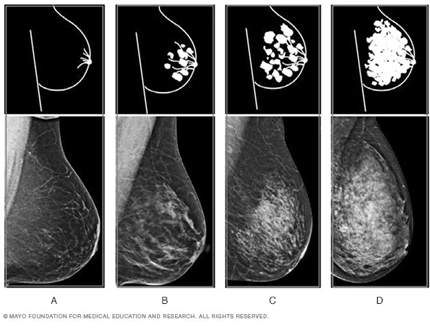

Existen cuatro categorías de densidad:

• A: Completamente graso (transparente)

• B: Fibroglandular disperso (la proporción entre los tejidos es similar y podemos ver a través de é).

• C: Heterogéneamente denso: Es mayor la cantidad de tejido denso, que le graso, se pude recomendar ultrasonido para complementar.

• D: Extremadamente Denso: Es significativamente mayor la cantidad de tejidos densos. Se recomienda incluir tomosíntesis (3D) y realizar ultrasonido.